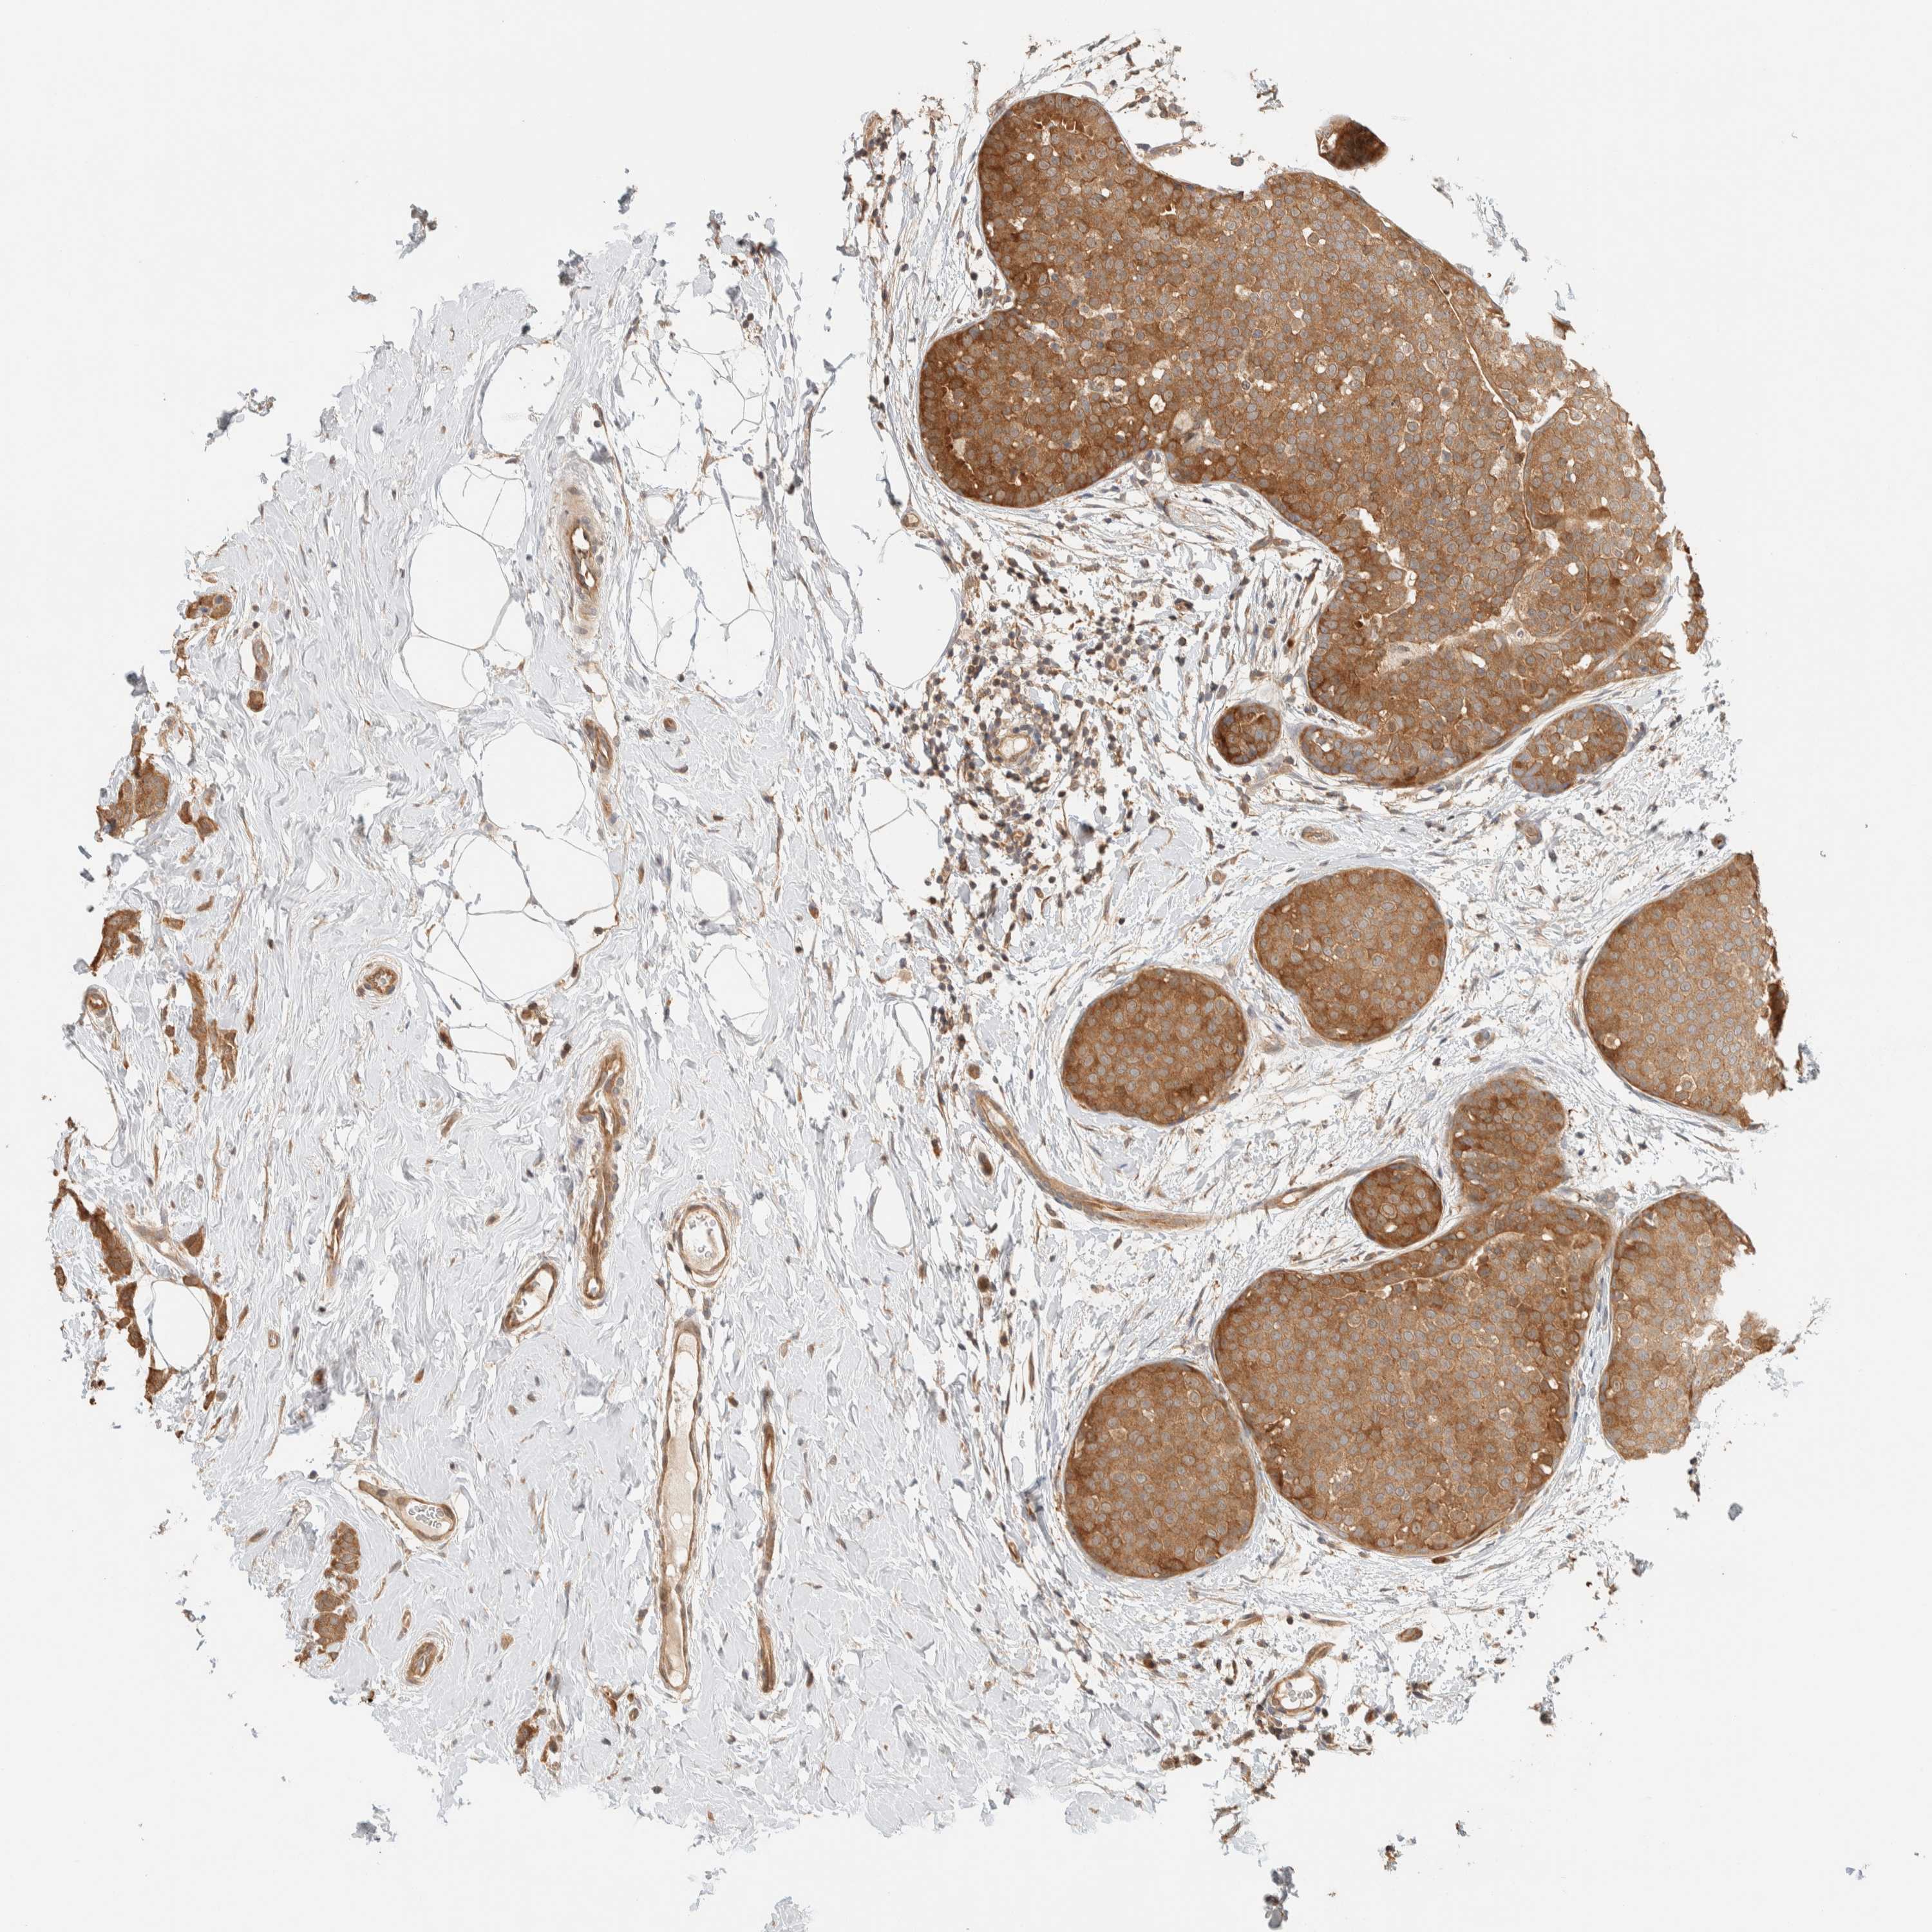

BRCA TCGA BRCA VALIDATION PROTEIN EXPRESSION